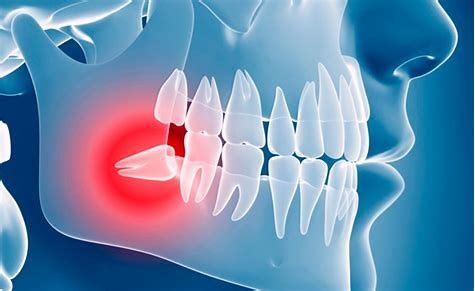

Si no hay suficiente espacio para que salgan, o si salen en una posición incorrecta, las muelas del juicio pueden provocar problemas. Si tu dentista dice que tus muelas del juicio están retenidas, quiere decir que están atrapadas en tu mandíbula o bajo tus encías. Lo anterior puede generar muchos problemas para la salud de tus dientes, como los siguientes:

En los casos en que estas piezas no están en la posición correcta pueden permitir que la comida quede atrapada. Esto permite a las bacterias que causan caries un lugar para crecer a sus anchas, lo cual se manifesta con dolor, hinchazón y rigidez en la mandíbula.